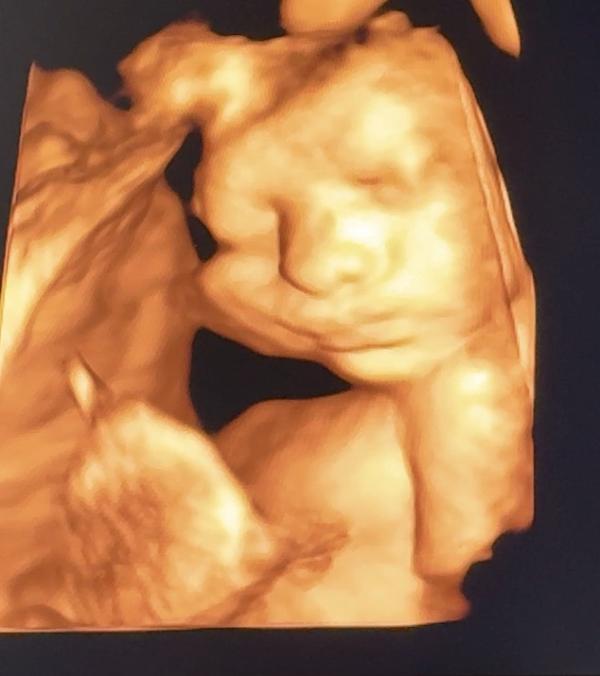

@elvira_fazylova, нам сейчас поставили авк((((( полной формы

@seaksea правильно делаете что ищите еще специалиста узи. Когда точно будете знать вид впс, можно будет поискать врача или центр, который на этом виде впс специализируется. Хотя я искренне желаю вам, чтобы они ошибались

В ркцп экспертное эхокг плода (мне делали там 3 врача) , если есть пороки они создают консилиум и приглашают кардиохирурга из кардиоцентра (чаще он просто онлайн) и решают дальнейшую тактику

P.S. наш порок сердца не подтвердился после рождения- хотя делали 3! Экспертных врача , дочка здоровая